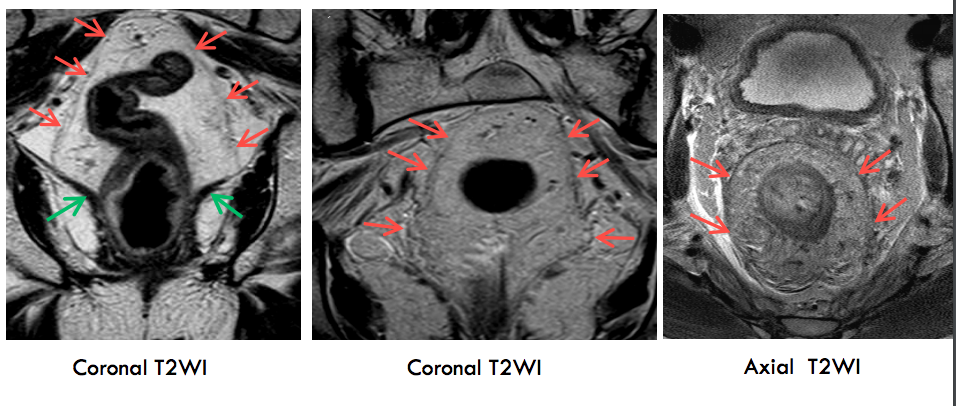

Hình 1. Các lớp giải phẫu của trực tràng tương ứng trên cộng hưởng từ

Hình 2. Các lớp giải phẫu trực tràng trên các chuỗi xung với mũi tên đỏ là cân mạc treo trực tràng (mũi tên đỏ)